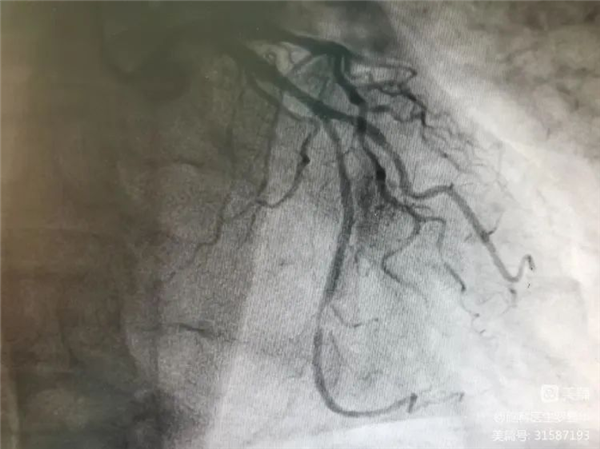

李東波副院長(zhǎng)團(tuán)隊(duì)正在為患者行頸動(dòng)脈支架植入術(shù) Xbg安康新聞網(wǎng)

手術(shù)過(guò)程:指引導(dǎo)管到位Xbg安康新聞網(wǎng)

手術(shù)過(guò)程:球囊擴(kuò)張后,protege支架到位Xbg安康新聞網(wǎng)

術(shù)后造影示狹窄解除Xbg安康新聞網(wǎng)